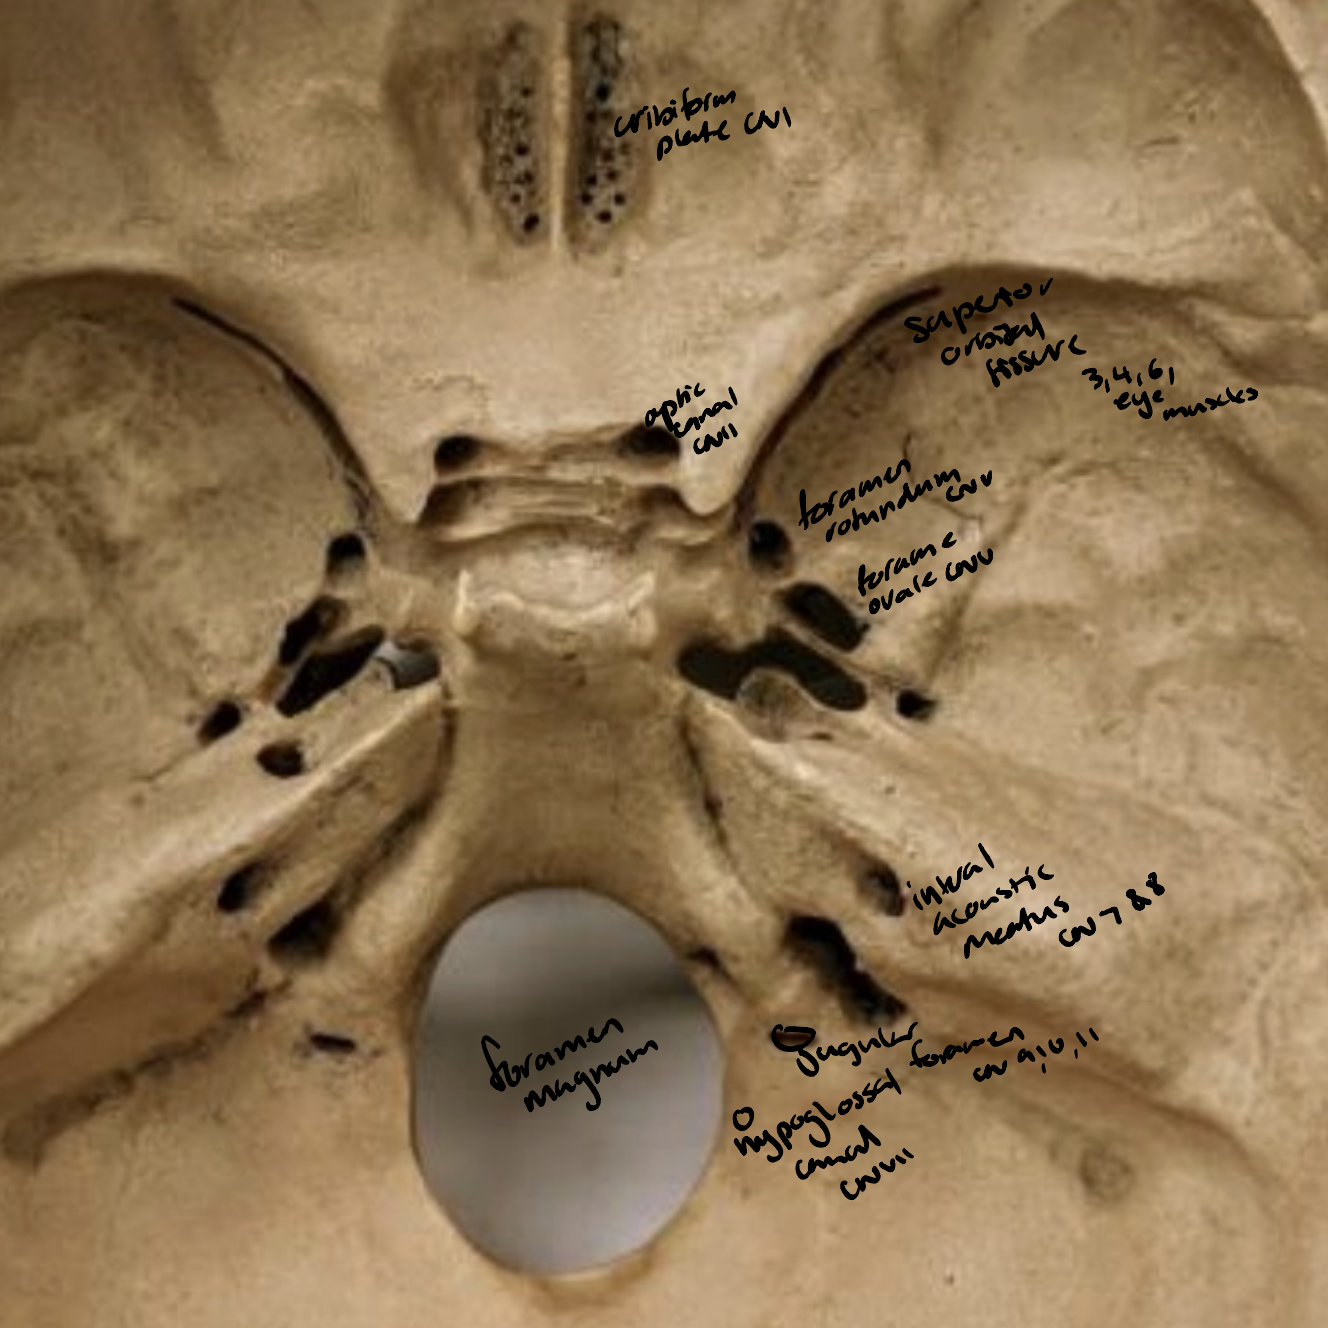

Cranial Nerves